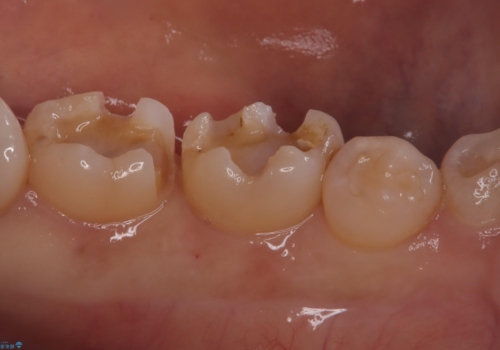

- 主訴:詰め物が外れた これを機に白い詰め物にやり替えたい

左下7番目の歯の詰め物が外れ、セラミックインレーでのやり替えとなりました。

隣在歯にも保険適用もメタルインレーが入っており、咬合面のインレーと歯質の境目が虫歯になっていたこともあり、合わせてのやり替えとなりました。

左下7番めの歯、フロスを通したらインレーが外れてしまったとのことで、適合具合の精密さや、これを機に白い詰め物にしたいとのことからセラミックインレーでのやり替えとなりました。

また、6番目の歯にも保険適用のメタルインレーが入っており、咬合面インレーと歯質境目にう蝕を認め合わせてのやり替えとなりました。